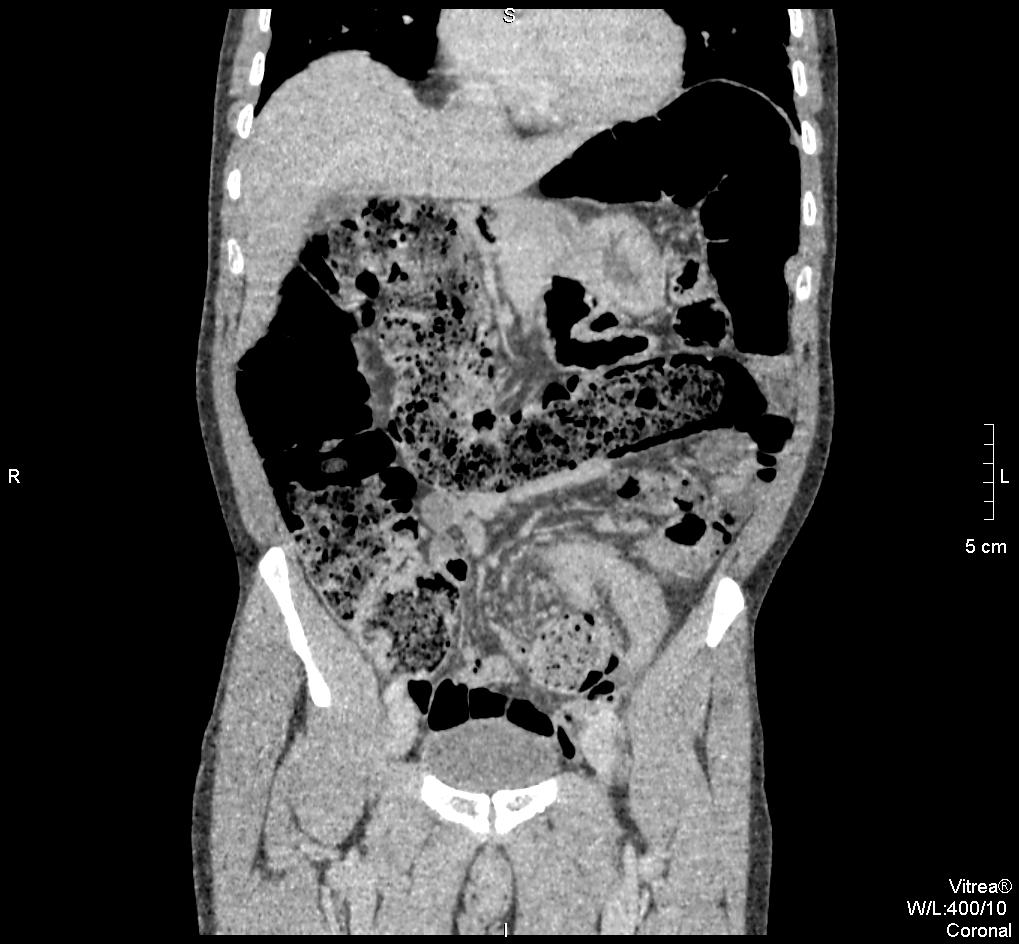

45 koruli ferfi. Elozmenyben hasi mutet nincsen. Ket napja puffad a beteg hasa, azota nincsen szeklet. A CRP minimalisan emelkedett, a FVS normalis. Laz nincsen, feszes, gazos has.

Vastagbel occlusio eseten vizsgalando:

– coecum a helyen van-e (volvulus coecalis eseten a bal hypochondriumban van)

– faecaloma

– ha a nativ hasi felvetelen kavebab-jel latszik, akkor sigma-volvulus

A zsirdenzitas a mesenterium „beforgasat” jelzi a belfal negyezte koze az organo-axialis formanak megfeleloen.

Azert nincs szep whirlpool sign = signe de tourbillone = orveny jel?, mert nem a mesenterium a forgastengely, hanem maga a sigma.